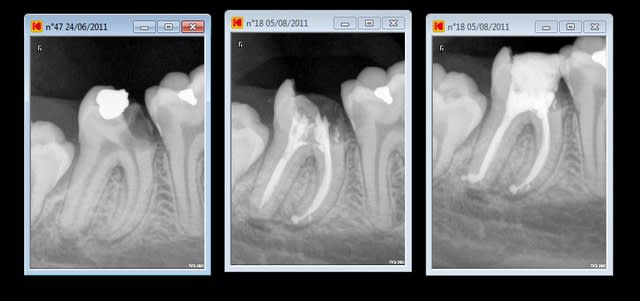

pourquoi l'endo au fait (nécrose racine distale de 46)

préparation Mtwo et j'aime bien .

05/08/2011 à 17h05

aujourd'hui dernier jour de travail

chui fainéant : pas mis la digue car il aurait fallu reconstituer cette dent avant

mais bon à quatre mains on a mal travaillé dans un premier temps et pi on s'est rattrapés.

pas tentés par le MTWO ???

Fouilla, désolé d'être un peu désagréable, mais faire une endo sans digue et qui plus est avec un manque TOTAL d'étanchéité en mésial, autant dire que c'est beau radiographiquement, mais nul d'un point de vue microbiologique. Quand je vois ça, ça me conforte dans l'idée qu'il faut toujours tenter de reprendre un traitement en cas d'échec, même s'il paraît bon (ou très bon) radiographiquement, car on ne connait jamais le niveau d'asepsie et d'antisepsie dans lequel ça a été réalisé sur la seule base de la vue d'une radio. C'est pourtant pas le temps que ça t'aurait pris en plus. Et puisle must : le petit compactage supplémentaire en voyant que le distal n'était pas aussi parfait que les mésiaux...avec un peu de salive en plus entre les deux radios...Merci de nous faire partager "ta fainéantise" avec franchise en tout cas.